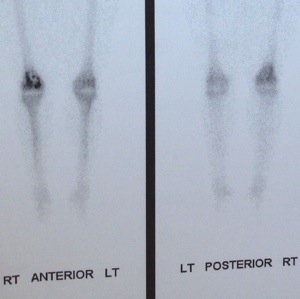

Monday I had a nuclear bone scan to see if there might be another bone tumor somewhere else.

Tuesday I saw the same orthopedist from last week to get the results from the previous two tests. Brought a friend with me just in case it was less than desirable news. (Thank you Miss Laura.) He gave me what I felt was the best news given the situation–that it looks from the bone scan that we are only dealing with one tumor and that from the MRI he could see that the tumor was still encapsulated in the bone. I also got the news that the orthopedic oncologist in New Orleans had an opening the next day–the one who originally I wasn’t going to be able to see for a month. What a great visit given the situation!